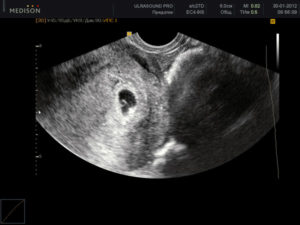

Также на сроке в 5 недель можно уже увидеть, ждёт будущая мама одного малыша или у неё будет двойня. Отличие в том, что плодных яйца будет два, а не одно.

Пол ребенка, конечно же, узнать не получится, так как половые органы еще только начинают формироваться, а вот обрадовать или озадачить будущих родителей тем, что растет и развивается двойня или даже тройня будет уже легко. Несмотря на то что размер плода не больше горошины, его маленькое сердечко уже бьется, но без ультразвука его услышать не получится.

- определить число плодных яиц, расположенных в матке;